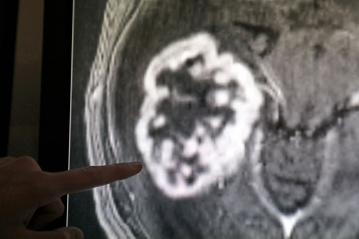

Positive Trends bei Kopf-Hals-Tumoren in Rheinland-Pfalz

Mainz. Kopf-Hals-Tumoren betreffen in Rheinland-Pfalz mehr Männer als Frauen, jedoch gibt es positive Trends, wie das Institut für digitale Gesundheitsdaten in Mainz mitteilte. Im Jahr 2024 wurden 429 Männer und 213 Frauen mit diesen Tumoren diagnostiziert, wobei 164 Männer und 73 Frauen daran starben. Männer sind nach wie vor häufiger betroffen als Frauen.

Die Auswertungen des Krebsregisters Rheinland-Pfalz zeigen insgesamt eine leicht positive Entwicklung. Bei Männern gehen die Inzidenzraten zurück, und auch bei Frauen ist ein rückläufiger Trend erkennbar, wenn auch weniger ausgeprägt. Die Sterberaten entwickeln sich unterschiedlich: Bei Männern ist ein leichter Rückgang zu beobachten, während sie bei Frauen weitgehend stabil bleiben. Auffällig ist, dass die Erkrankungen vor allem im höheren Lebensalter gehäuft auftreten, insbesondere in der Altersgruppe 70 bis 74 Jahre.

Kopf-Hals-Tumoren werden häufig erst in fortgeschrittenen Stadien diagnostiziert. Die Behandlungsqualität ist hoch: Mehr als 80 Prozent der Tumoren werden innerhalb von sechs Wochen operiert, und in über 90 Prozent der Fälle wird die Therapie innerhalb von 16 Wochen abgeschlossen. Diese Tumoren erfordern individuelle Behandlungen, oft kombiniert aus Operation, Bestrahlung sowie Chemo- und Immuntherapie. Fortschritte gab es bei chirurgischen Verfahren durch Laser- und roboterassistierte Techniken. Auch die Strahlentherapie wurde präziser und schonender, während Immuntherapien an Bedeutung gewinnen.